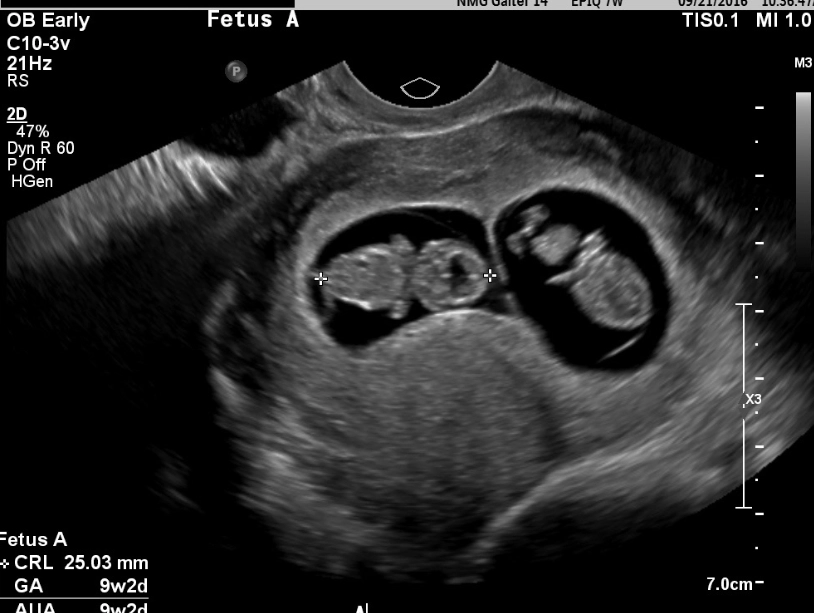

The big milestone: Your first-trimester screening (often between weeks 11-13) might include a nuchal translucency ultrasound and blood tests. This checks for certain chromosomal conditions. It can be an anxious wait for results, but also incredibly special—you might get to see your baby bouncing around!